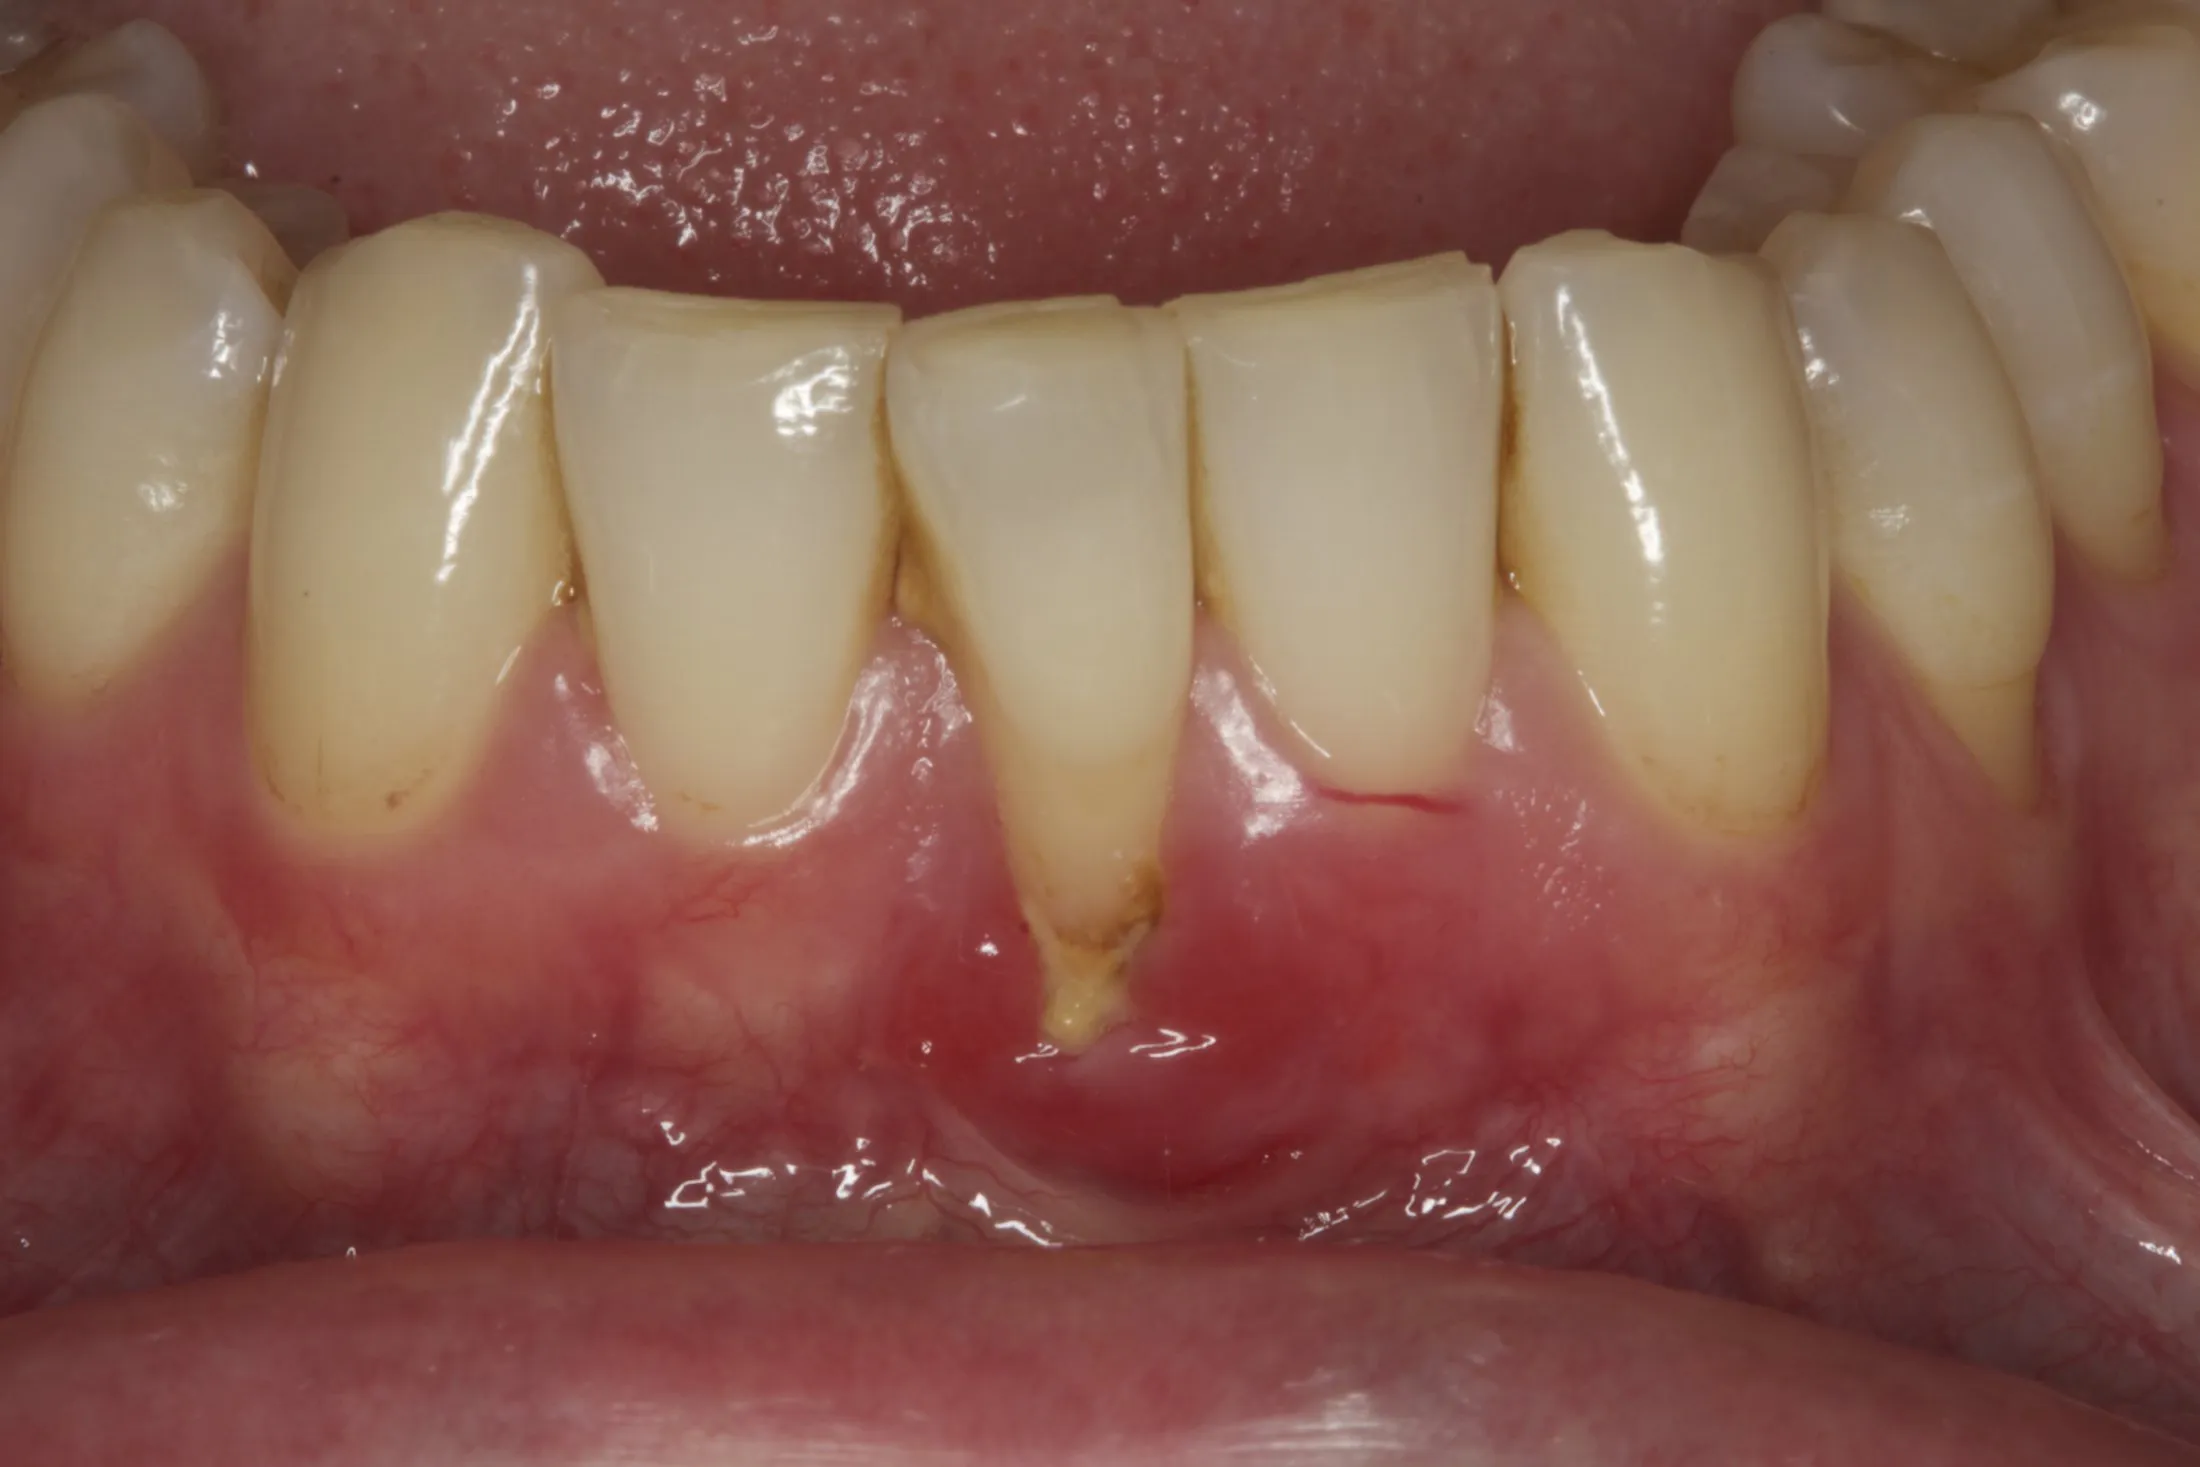

Connective Tissue Gingival Grafting for Gingival Recession